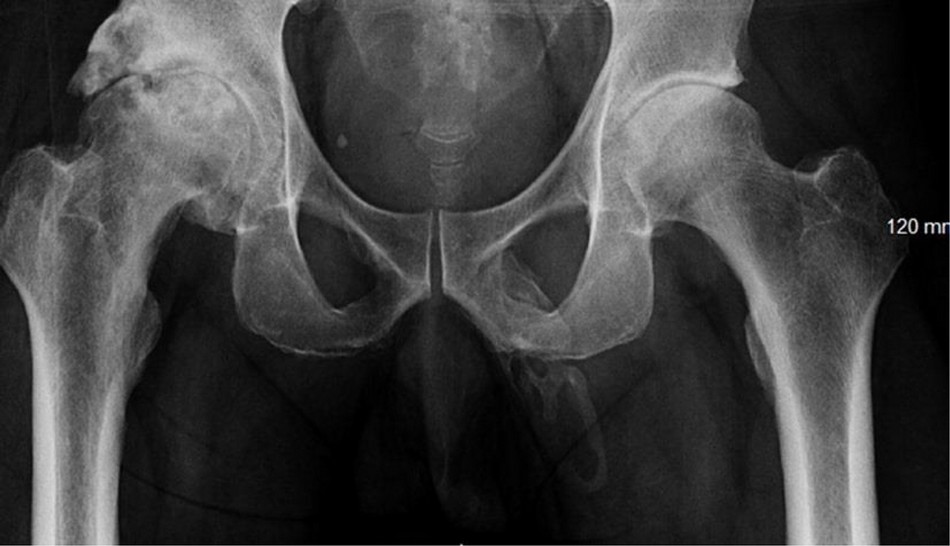

The doctors found this case extremely rare when they performed a radiograph of the pelvis, in order to look for signs of bone fracture. But instead, they spotted a bone-like calcification in a most unexpected place ...

Calcium salts have accumulated in soft tissues and have hardened to form an "extended plaque" along the penis stem, as you can see on the radiograph below:

Except for some pain, the patient has no other symptoms of this condition in the form of discharge or swelling. According to the doctors, ossification of the penis can cause a loss of flexibility and also cause erectile problems. But before the doctors could do further examinations, including to determine the cause of this ossification, the man decided to leave ignoring all the medical advice he had received from the doctors ...